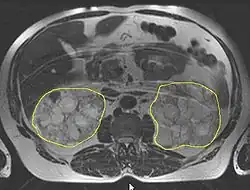

Die Diagnose wird in der Regel durch eine Sonografie („Ultraschall“)[14] oder durch andere bildgebende Verfahren, wie beispielsweise die Magnetresonanztomografie, gestellt.[15] Mit der Sonografie können mit modernen Geräten Zysten bis herab zu einer Größe von 5 mm diagnostiziert werden. Die Früherkennungsrate bei 20-jährigen Patienten liegt bei etwa 90 %.[16] Die Computertomografie bietet zwar eine höhere Auflösung mit besserer Bildqualität, sie wird jedoch vor allem wegen der Strahlenbelastung nicht für Patienten-Screenings, sondern nur bei speziellen diagnostischen Fragestellungen eingesetzt.[3]

Die Entstehung und Entwicklung von Zystennieren, die Pathogenese, beruht auf einer zystischen Degeneration der sogenannten Nierenkanälchen (Tubuli, auch: Harnkanälchen) in den Nieren. Diese führt bei der autosomal-dominant vererbten PKD im Verlauf von Jahrzehnten zu einer zunehmenden Vergrößerung der Nieren. Es kann dabei zu einer Funktionseinschränkung bis hin zum völligen Verlust der filtrativen Nierenfunktion kommen. Beide Nieren sind gleichmäßig betroffen. Mehrere hundert Zysten, die in ihrer Erscheinung prall elastisch sind, können dabei pro Organ ausgebildet werden. Masse und Volumen der Nieren können dadurch erheblich anwachsen. Während eine gesunde Niere durchschnittlich eine Masse von 160 g aufweist, können polyzystische Nieren bis zu 8 kg bei bis zu 40×25×20 cm³ (= 20 Liter) Volumen erreichen (gesunde Niere: 12×6×3 cm³ = 0,216 Liter). Trotz des erheblich gesteigerten Platzbedarfs des Organs kommt es nur relativ selten zu Funktionsstörungen der benachbarten Organe.[24]

Die Zysten finden sich sowohl am Nierenmark (Medulla renis) als auch an der Nierenrinde (Cortex renalis). Prinzipiell kann dabei jeder Bereich eines Nephrons eine Zyste ausbilden. Bevorzugt betroffen sind jedoch die Glomeruli und die Henlesche Schleife. Gefüllt sind die Zysten mit dem sogenannten Tubulusharn. Der Durchmesser einer einzelnen Zyste kann von wenigen Millimetern bis über 100 mm sehr stark variieren. Große Zysten können so mehrere hundert Milliliter Tubulusharn enthalten. Das Innere der Zysten besteht aus einem einschichtigen Plattenepithel oder einschichtigem isoprismatischen (kubischen) Epithel. Mit dem Fortschreiten der Erkrankung können sowohl die Anzahl als auch die Größe der vorhandenen Zysten zunehmen.[3]